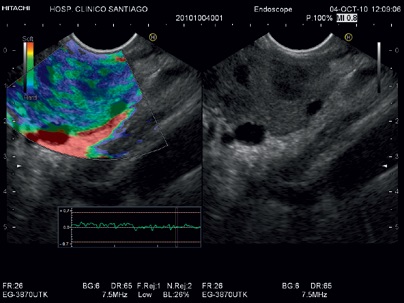

Модель EG-3870UTK использует искривлённый линейный датчик ультразвука, который обеспечивает большое поле зрения в 120° с исключительным качеством изображения, что дает возможность эндоскописту достичь высокого уровня диагностической точности при всех разрешённых показаниях. С поддержкой различных технологий обработки изображения, таких как эластография в реальном времени компании Hitachi (HI-RTE) и функцией Доплера, возможна более точная локализация и прицеливание к очагу поражения.